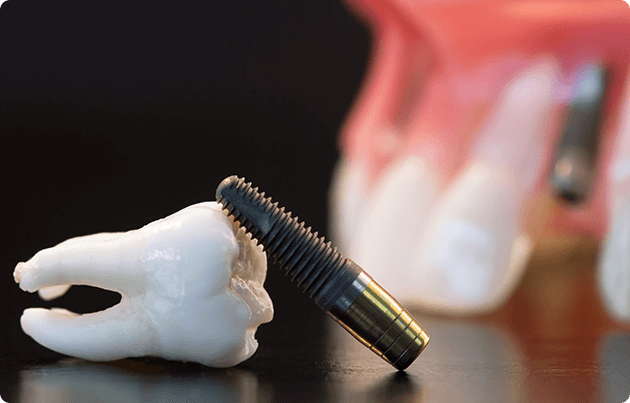

歯を抜くと同時にインプラントを埋入する治療法です。

一般的なインプラント治療は、手術から仮歯を入れるまで3~6カ月の安静期間が必要でしたが、即時荷重インプラントであれば当日中に仮歯を装着することができます。